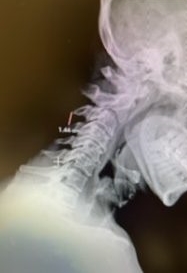

This 57 year-old male presents with severe neck, left shoulder and arm pain and weakness in his hand since being involved in a motor vehicle accident nine months prior. The patient had subsequent left shoulder surgery although he still complained of pain postoperatively and his weakness persisted. He was on no blood thinners. He underwent imaging. The cervical spine MRI revealed an extensive dorsal epidural collection from C1-2 through C5 with associated spinal cord compression. In addition there were multisegmental degenerative changes with foraminal stenosis worse at C4-5 (Fig. 1a and 1b).

(1a) Sagittal and axial T2-weighted cervical MRI demonstrating extensive dorsal epidural collection with hyperintense signal consistent with fluid causing spinal cord compression.

(1b) Hyperintense signal (arrow) at the C3-4 interspinous space consistent with ruptured interspinous ligament,C4-5 (Fig. 1a and 1b).

The fluid was possibly consistent with CSF versus chronic hematoma. The patient was also noted to have a high signal within the interspinous space of C3-C4. This high signal was consistent with a ruptured C3-4 interspinous ligament. Cervical flexion-extension x-rays demonstrated 6 mm of widening of the C3-4 interspinous space on flexion x-ray consistent with cervical instability (Fig. 2a and 2b).